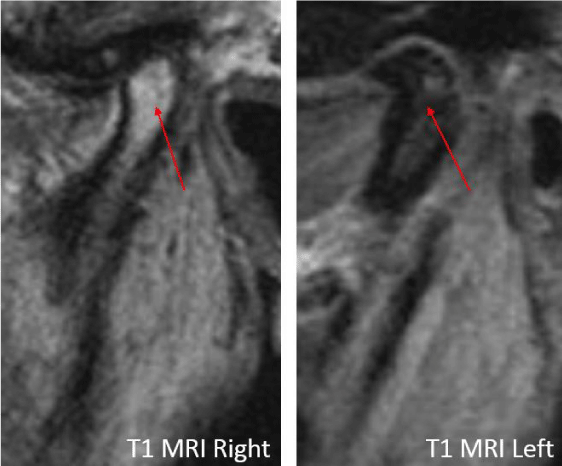

A 53-year-old male presented with a complicated musculoskeletal history consisting of head and neck dystonia and suprahyoid musculature spasms resulting in painful recurrent mandibular subluxation. Examination revealed a mouth-opening of 60 mm with ongoing subluxation due to muscle spasms. The CT scan of the left side suggested severe degenerative changes with multiple rounded erosive foci and a hazy periosteal reaction at the skull base (Figure 6). The T1 weighted MRI showed low signal intensity in the condylar bone marrow on the left. The disc was not visualized and there was no evidence of intra-articular mass (Figure 7). Diagnostic arthroscopy of the left showed a large central perforation of the disc with remarkable nodular synovitis. Synovial biopsy, synovectomy and debridement were performed (Figure 8). Histologic examination showed PVNS (Figure 9). Additional surgical treatment for the dislocation and the degenerative changes of the TMJ was deferred until further control of the muscular dystonia was achieved.